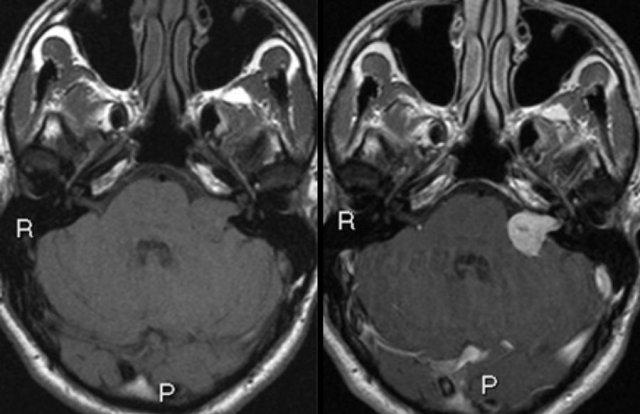

U schwannoma tiền đình bên trái. Hình ảnh cắt ngang chuỗi xung T1W không tiêm thuốc tương phản từ (trái) và có tiêm thuốc tương phản từ (phải).

MRI chỉ được khuyến cáo ở những bệnh nhân ù tai (không mạch đập) một bên kèm theo các bất thường thần kinh khu trú, hoặc mất thính lực không đối xứng [4].

Mục đích chính của chẩn đoán hình ảnh là xác định hoặc loại trừ tổn thương tại bể góc cầu tiểu não (ví dụ: u schwannoma tiền đình).